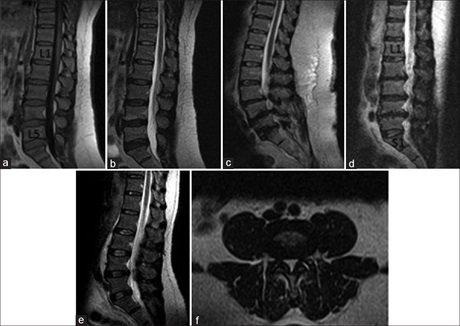

Cross-sectional Study on Incidental Spinal Findings in Magnetic Resonance Imaging Lumbar Spine of Patients with Low Back Pain

Dr. Binoj Varghese, Arun C Babu, Ashok Kumar, PS Priya, Jaison S John, Mohammed Noufal, KM Sivasubramaniyan (Author)

38-44

Magnetic Resonance Imaging of Lumbosacral Intervertebral Discs in Nigerians with Low Back Pain

Ademola Joseph Adekanmi, Temitope Olugbenga Bello , Dr. Omolola Mojisola Atalabi, Kamaldeen O Jimoh, Oluremi Ayotunde Ogunseyinde (Author)

61-67

Pattern of Lumbosacral Magnetic Resonance Imaging Findings in Diagnosed Cases of Disc Degenerative Disease among Nigerian Adults with Low Back Pain

Uzoamaka Rufina Ebubedike, Eric Okechukwu Umeh, Godwin I Ogbole, CA Ndubuisi, Wilfred C Mezue, Samuel C Ohaegbulam (Author)

25-29